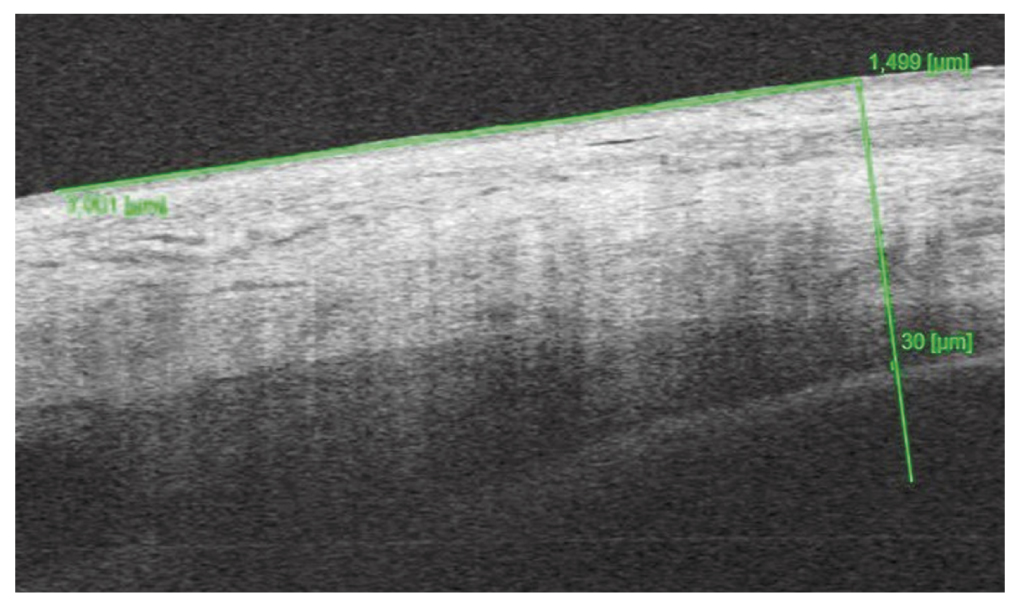

ОКТ переднего отрезка глаза по предлагаемому способу. OD: толщина сосудистого слоя цилиарного тела во внутреннем отделе 38 мкм (рис. 6), в наружном отделе — 34 мкм; OS — 39 мкм и 30 мкм соответственно; ОКТ заднего отрезка глаза без особенностей.

Рис. 6. Толщина сосудистого слоя цилиарного тела во внутреннем отделе правого глаза на 30-й неделе беременности

Fig. 6. Thickness of the vascular layer of the ciliary body in the inner part of the right eye at 30 weeks of gestation

Установлен диагноз: «Препролиферативная диабетическая ретинопатия обоих глаз».